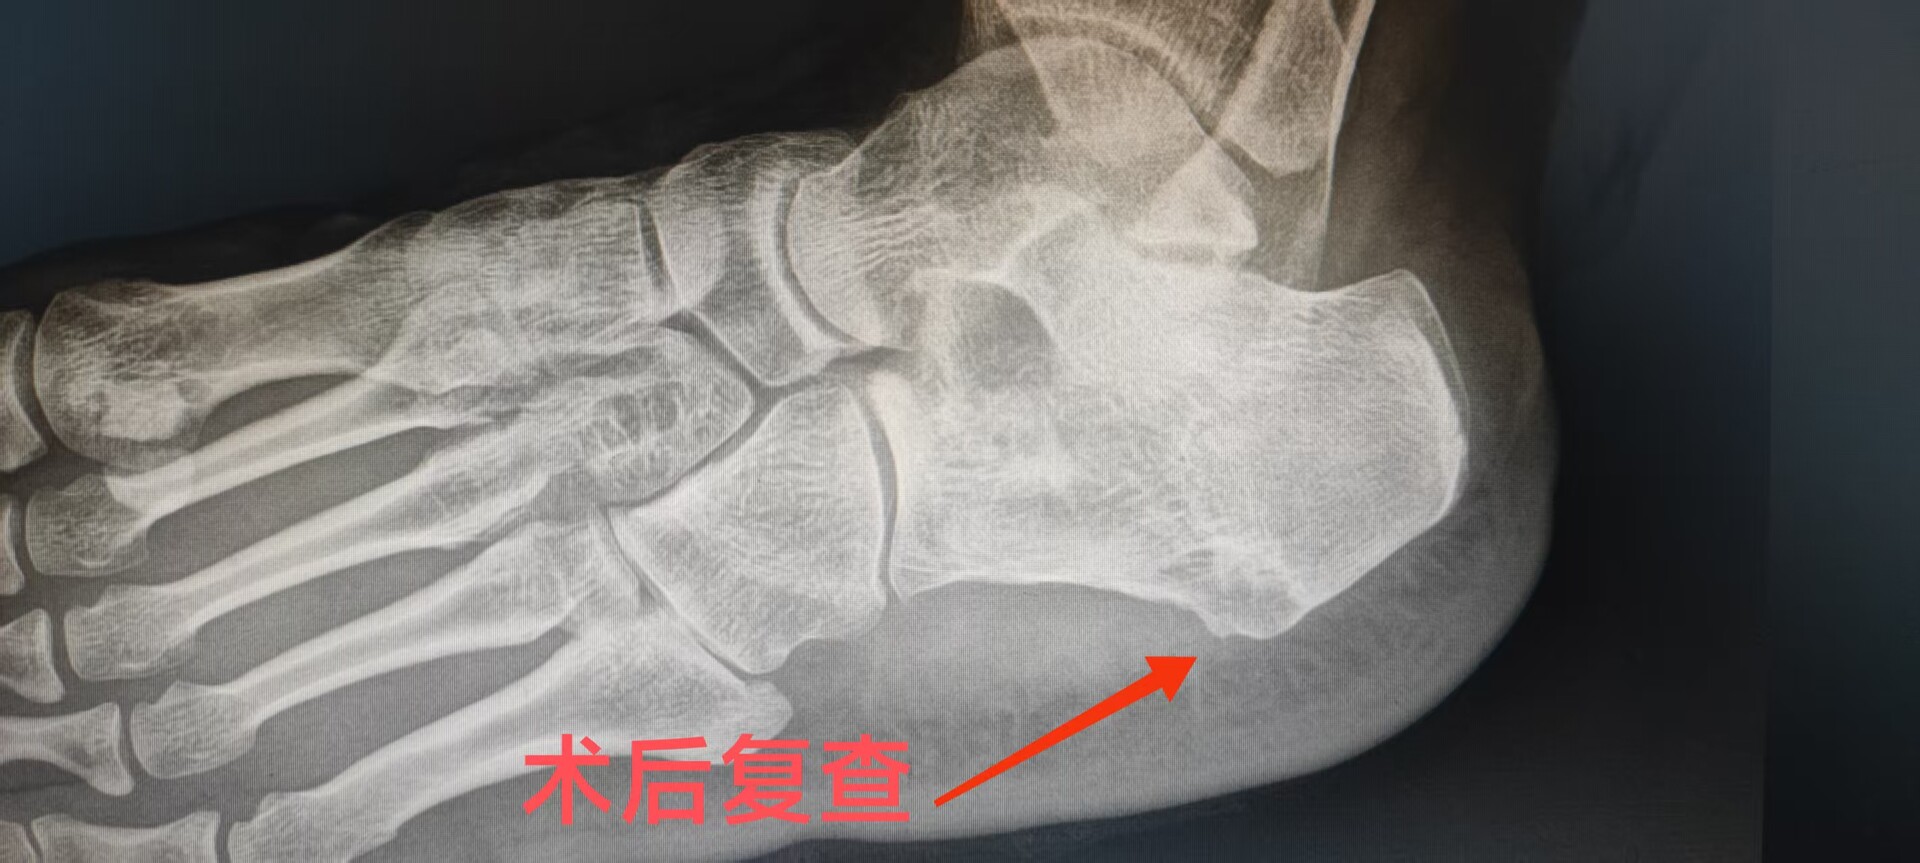

患者李女士被左足跟疼痛困扰了5年多,尤其是晨起下床的第一步疼痛最为剧烈。她尝试过冲击波、封闭针和理疗,但症状反复,最近甚至开始跛行,生活质量大受影响。术前X光显示,她的跟骨结节处有明显的“鸟嘴状”骨刺。

针对该患者的情况,永兴县人民医院骨科团队采用了目前国内先进的全关节镜微创技术,术中仅在患者足跟内侧开了两个约1厘米的小切口,这种微创技术最大程度保护了足部功能。而以往的传统开放手术,需要在足跟内侧切开3到5厘米的口子,虽然能切除骨刺,但创伤大、恢复慢,还容易损伤神经,可能导致术后足跟麻木或留下顽固的瘢痕痛。与传统开放手术相比,该技术实现了三大突破:创伤更小、恢复更快、理念更新——从单纯“取刺”升级为“功能重建”。患者术后次日即可下地行走,康复周期缩短约70%。